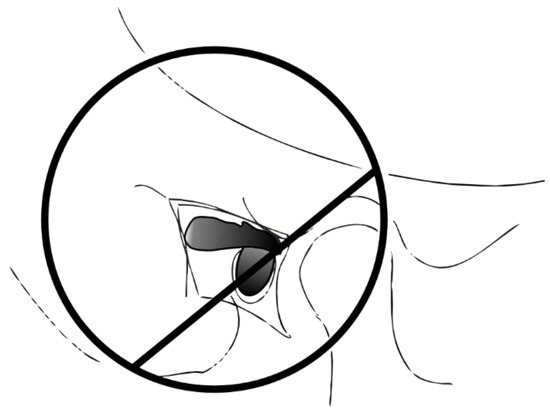

| a | ![]() A P€ = 99.4% | ![]() α P€ = 0.6% |

| b | ![]() B P€ = 98.6% | ![]() β P€ = 1.4% |

| c | ![]() C P€ = 92.1% | ![]() γ P€ = 7.9% |

| d | Imposible event P€ = 0% | ![]() δ Certain event P€ = 100% |